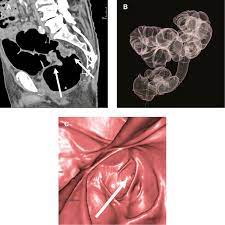

Colon Cancer Ct Scan Stock Image C047 9257 Science Photo Library from media.sciencephoto.com This screening test allows your doctor to carefully examine your colon for signs of polyps (abnormal growths on the inside surface of the colon that below, you can learn about the different types of screening tests for colorectal cancer. What are hereditary colon cancer syndromes? Knowing this helps you and your doctor choose the best treatment options. Ct scanners first began to be installed in 1974. It usually begins as small, noncancerous (benign) clumps of cells called. Feline cancer initially manifests as a lump or bump on any parts of the body. Ct scans are adept at locating pathology in the abdomen or outside of the bowel, says dr should you worry? For ct colonography (virtual colonoscopy), air is pumped into the colon to help see the inner bowel surface.

Imaging Of Colorectal Cancer The Clue To Individualized Treatment from www.degruyter.com Staging tests may include imaging procedures such as abdominal, pelvic and chest ct scans. Ct scan result colon cancer staging. Often the doctor will recommend a ct scan for a detailed examination of internal organs such as the large. A ct scan can often detect evidence of a growth or tumor. Colon cancer refers to cancer diseases that occur in the large and small intestine. If my own mother asked me what she should do to prevent colon cancer, i would tell her to this test is essentially a cat scan of the colon, designed to find large polyps and cancers. Find out about symptoms and risk factors for colon cancer, also called colorectal cancer. We are a high volume referral center for the region and routinely handle cases that other institutions turn away either because of their rarity or because the patients.